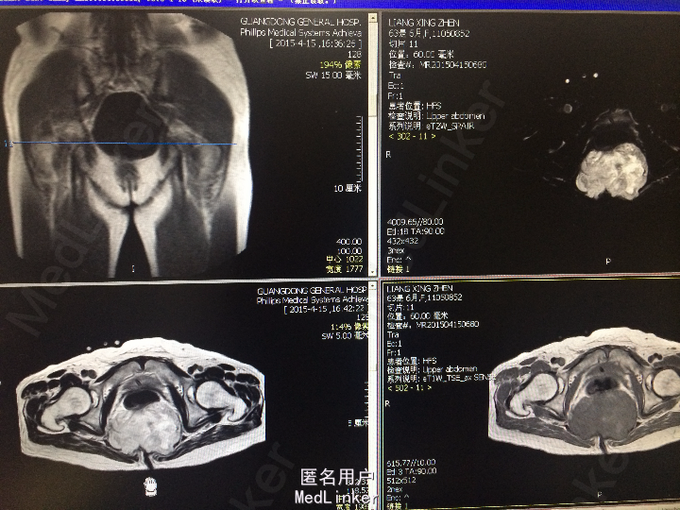

老年女性 主诉:腰背痛半年余,大小便失禁1周。 病史:患者于半年前腰部扭伤后,出现腰痛、腰部无力,需借助外力站立和行走。自诉四肢肌肉力量间断出现减弱,容易出现肌肉僵直,并有肌肉颤动感。半年来,患者多卧床休息,未接受正规治疗。10余天前,出现胸部疼痛,并向背部放射,病人烦躁、易怒,难以入睡、胃纳差、大便次数少。1周前出现大小便失禁,体重近1月下降10余斤。

查体:脊柱生理弯曲存折,腰椎棘突间触痛(-),双侧腰椎旁叩痛(-),活动自如,关节无红肿,双侧下肢肌群肌力正常,双侧下肢外侧皮肤痛、温觉正常,未引出病理性反射,尾骨未触及。 辅查:外院X线:腰骶角增大,提示腰椎失稳可能;腰椎轻度退行变;S3以下骨质结构缺如。

诊断:骶尾部肿物:脊索瘤? 处理:完善各项检查后,为明确具体病理类型行骶尾部肿瘤穿刺活检术,病理明确后行腹腔镜辅助下骶尾部肿瘤切除术。

脊索瘤起源于胚胎残留的脊索组织。50 %的脊索瘤都发生在人体骶尾部。如果肿瘤侵犯脊柱,通常可出现脊髓压迫征,直接浸润,累及腹膜后组织,肿瘤足够大时,可以造成肠腔狭窄,或侵犯膀胱。就骶尾部脊索瘤的治疗方面而言,手术治疗解剖位置深在,手术暴露困难,加之起病隐匿,病程较长,患者来诊时肿瘤已经广泛侵犯周边组织,因此手术难度较大。该病人肿瘤尚完整,除骶骨骨质外未见侵犯其他组织,因此手术切除仍为较好的治疗方法。术后可加用辅助放疗可降低复发率。